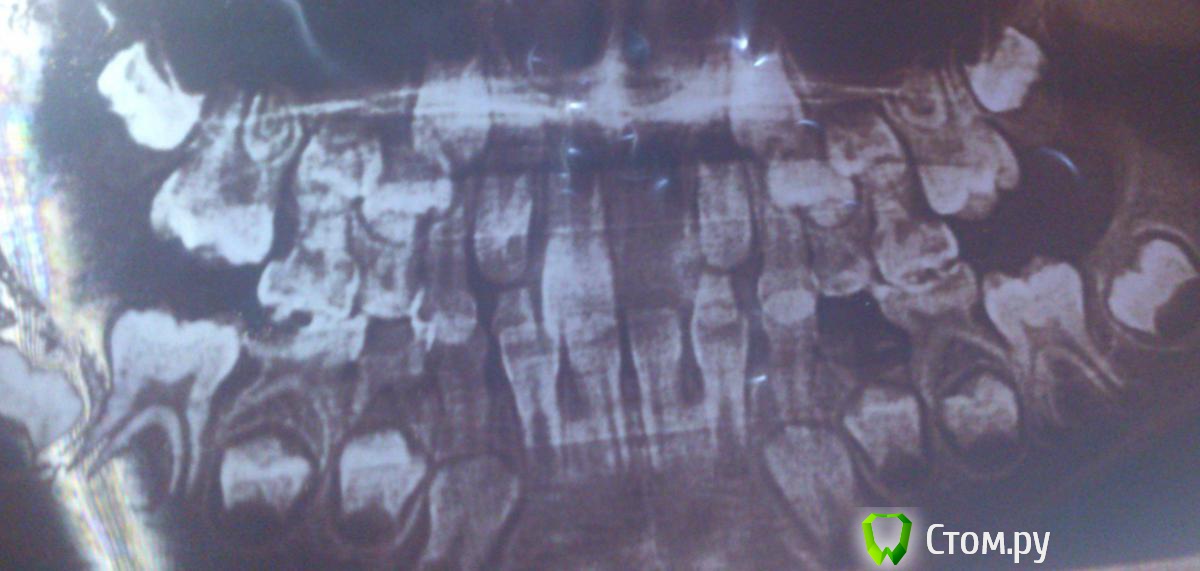

m.d.n Опубликовано 18 марта, 2014 Поделиться Опубликовано 18 марта, 2014 ЛМ активатор - какие показания для 6-летнего ребенка?по этим фото у ребенка 2 класс Ссылка на комментарий

Force Опубликовано 18 марта, 2014 Поделиться Опубликовано 18 марта, 2014 По этим фото у ребенка сменный прикус. Кейс не задокументирован по правилам, если вы хотите назначать лечебный аппарат. Подбор ЛМ-активатора осуществляется врачом на основании ДИАГНОЗА (включая цефалометрию). А по поводу показаний к лечению дистального прикуса (неподтвержденного и неочевидного), существуют разные мнения. Скорее всего, в данном случае в данном возрасте их не будет. Я это все к тому, что не стоит так швыряться назначениями. Ссылка на комментарий